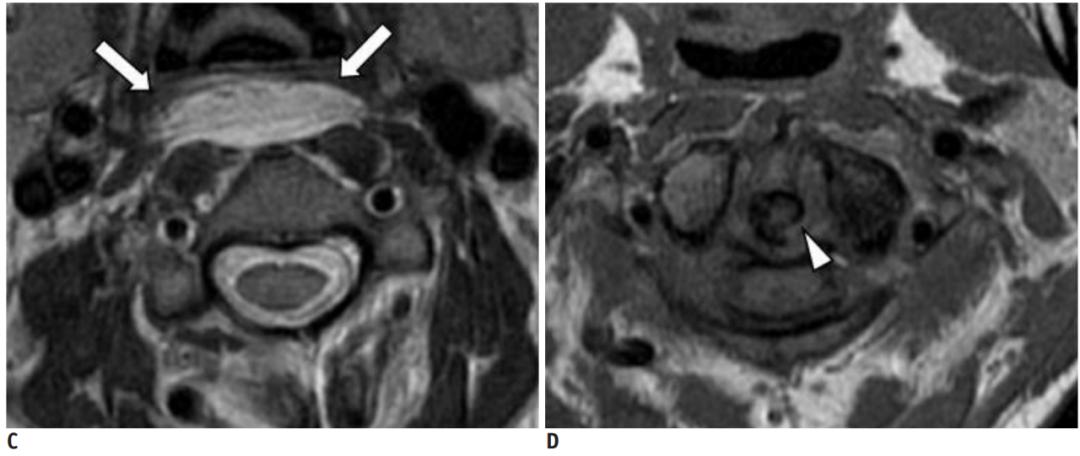

36岁女性,急性颈痛、吞咽困难伴颈部僵硬,MRI示C1-2前部颈长肌增厚呈低信号,提示钙化(长箭头)和C1-4椎前积液(无线箭头),经类固醇和止痛药治疗8天后症状消失,复查MRI提示上述表现消失。(PMID: 18765656)

C1-2前侧低信号(无线箭头)和C1-5椎前水肿(长箭头) (PMID: 19567634)

30岁女性,诊断为颈长肌钙化性肌腱炎,但钙化位于不寻常的位置:C4-5椎间隙前侧。A:颈椎侧位片示寰枢椎半脱位(长箭头)和椎前软组织肿胀(无线箭头);B,C和D:颈椎MRI示C1-6椎前软组织肿胀伴积液,D示齿状突骨侵蚀(无线箭头)